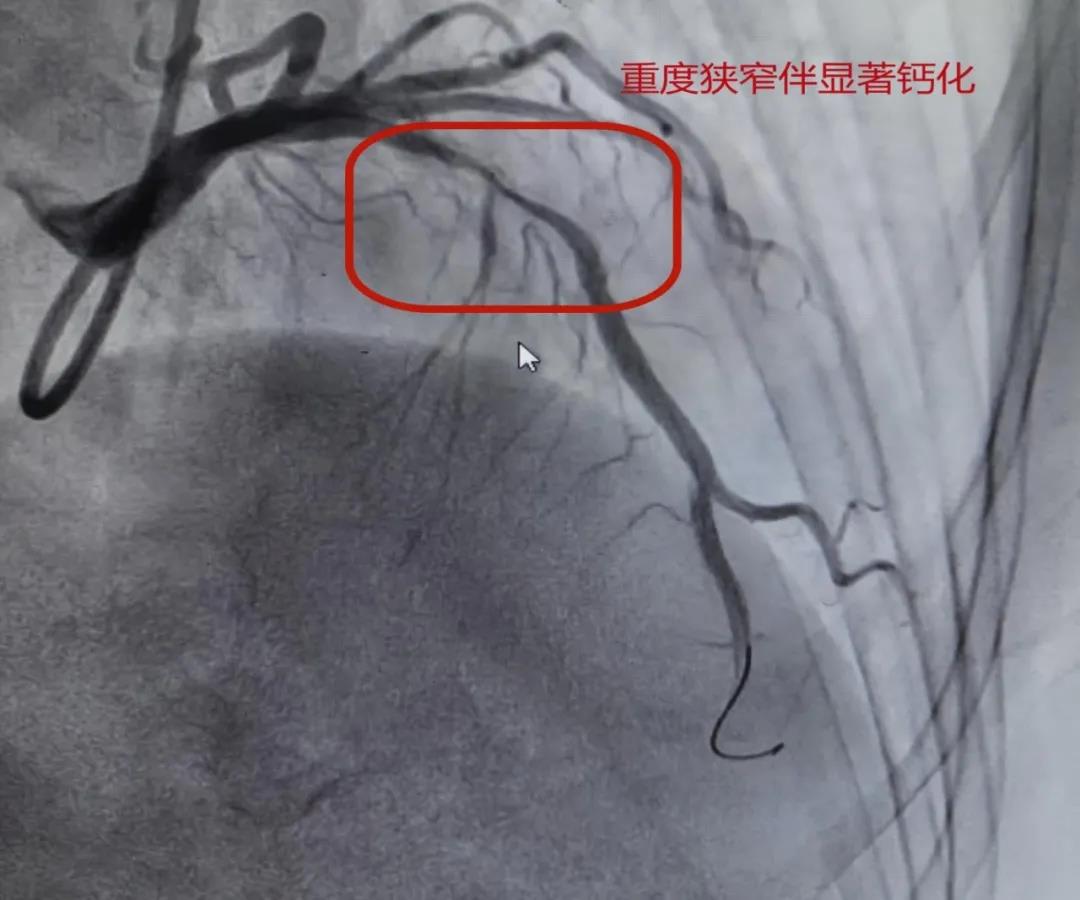

接受手术的患者因“反复胸闷、胸痛”入院,冠脉造影检查提示,患者其前降支近段存在重度狭窄,并伴有严重的环形钙化,就像年久失修的水管里长满坚硬水垢,形成了“石头隧道”。对于这种严重钙化病变,单纯使用球囊难以充分扩张血管,还可能增加血管撕裂、夹层等并发症风险,对手术带来较大挑战。

面对这一棘手难题,心血管内科介入团队经过缜密评估,决定采用冠状动脉旋磨术为患者打通血管。为精准评估病变情况,介入团队首先采用血管内超声(IVUS)检查。IVUS能够清晰显示患者血管内的钙化呈360°环形、范围广泛,最小管腔面积仅为2.01mm²。通过细致评估,团队精确测量了血管直径、钙化厚度及管腔面积,为后续治疗策略的制定提供了重要依据。